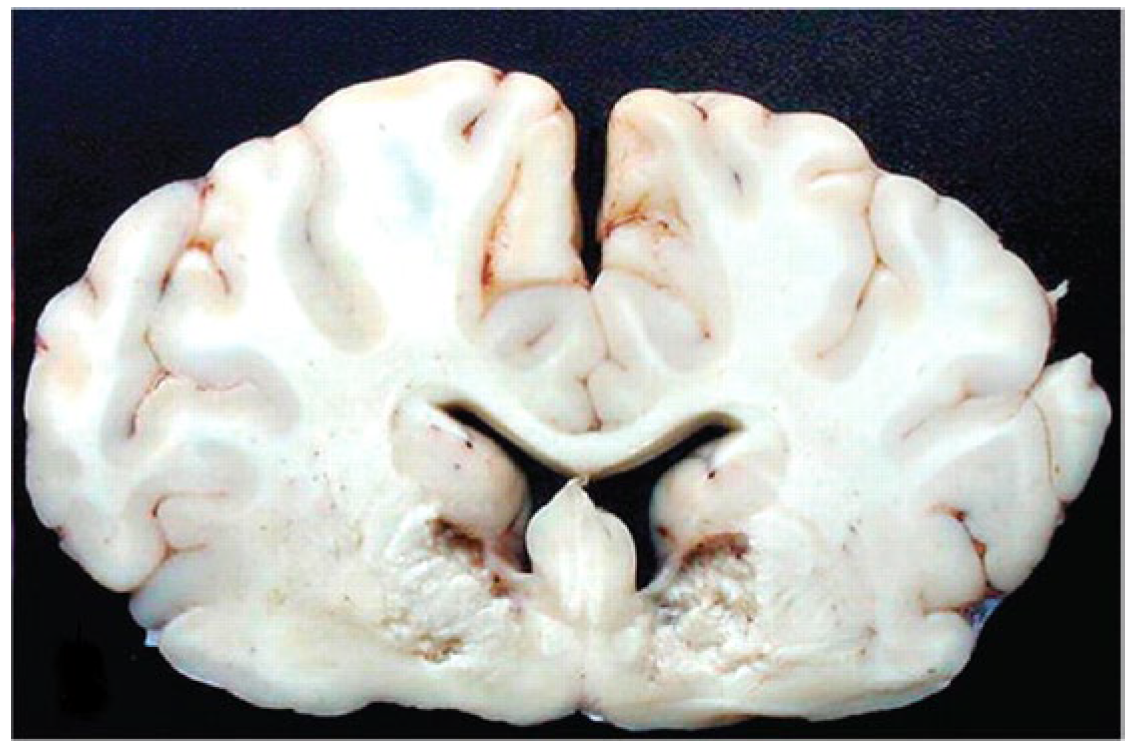

In cattle in Brazil, under natural conditions and in most cases, the death of animals occurs during the first six to 18 hours, but if they survive for more than 36 to 48 hours, necrosis of the brain tissue occurs, known as focal symmetric encephalomalacia (Figure 7). The most common clinical form is super-acute, with death within four to eight hours, and neurological changes such as opisthotonus and pedaling movements can be observed; and respiratory changes such as tachypnea and pulmonary edema. At necropsy, findings may not be very evident, but in some cases hydrothorax, hydropericardium, hydroperitoneum, pulmonary edema and cerebellar hernia are found. Histopathological lesions are neurological lesions being restricted to histopathological findings of eosinophilic proteinaceous perivascular edema or microangiopathy, and focal symmetric encephalomalacia [6,27,28,29,30,31,49,50,51].

Figure 7. Focal symmetrical encephalomalacia. This animal developed progressive neurologic signs that became very severe 8 days after inoculation, at which time the calf was euthanatized [49].